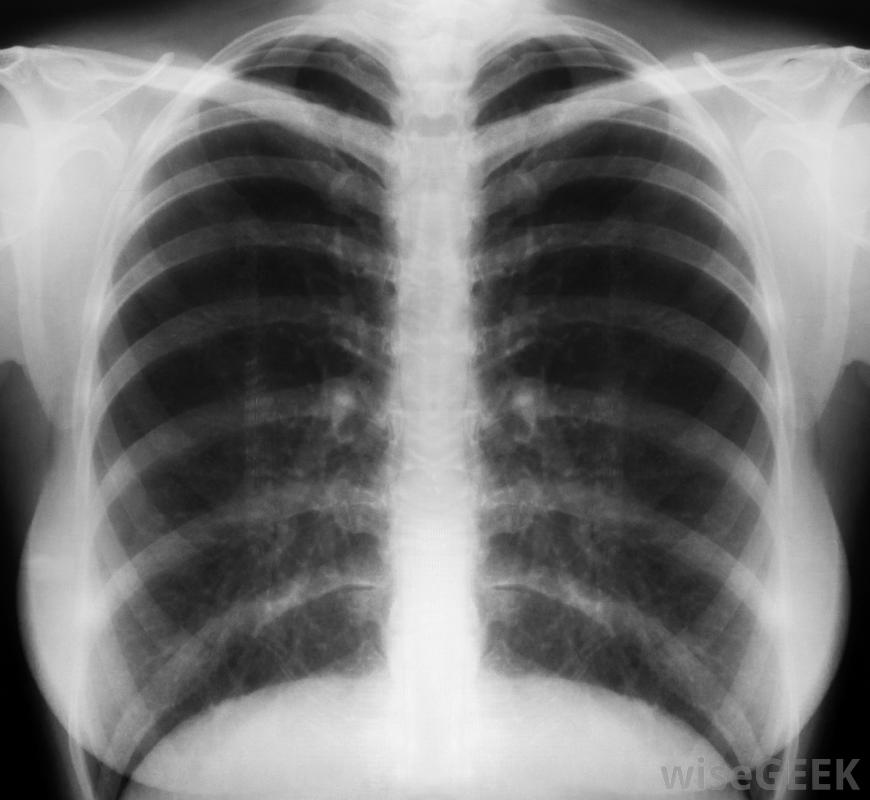

腺癌通常采用化疗和放疗相结合的治疗方法。除吸烟外,接触氡气或石棉也会增加人患肺腺癌的风险。这种疾病的症状可能包括呼吸急促、咳嗽不停、咳血和胸痛。更常见的癌症症状,如疲劳和体重减轻,肺腺癌在大多数情况下进展相对缓慢,因此在肿瘤扩散或转移之前,症状可能不会出现,吸烟通常被认为是肺癌的主要病因,当肺腺癌转移时,大约有一半的时间会扩散到大脑,与另一侧的肺一起扩散,肝脏和骨骼是其他可能的部位。诊断腺癌的检查通常包括胸部X光片和支气管镜检查,将一个薄而灵活的望远镜插入肺部,将图像传回给外科医生,并使肺组织的样本能够被移除有时,如果使用支气管镜无法触及肿瘤,则将针头穿过胸壁以获取组织样本。

胸部x光片可用于帮助诊断腺癌。